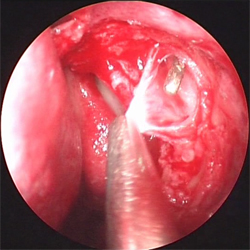

淚囊腫瘤根據病史及臨床特徵,結合影像學表現,可以明確淚囊部腫瘤的診斷但確診腫瘤的性質需要病理學檢查

淚囊腫瘤的一個重要特點是淚囊部腫脹因而首先應與淚囊炎相區別。因所有腫瘤的病程都比較長沒有急性炎症現象故易與急性淚囊炎區別慢性淚囊炎通過淚道沖洗和擠壓便可診斷因為淚囊炎在擠出膿液後就癟陷而腫瘤則不可能與慢性淚囊炎另一區別是後者淚囊區一般未捫及包塊壓之為灰白色黏液或膿液自淚點流出X線拍片,淚囊窩骨質無破壞,淚囊造影顯示淚囊排空緩慢側位見造影劑環繞腫塊可助區別所有的良性腫瘤的腫脹部位在內眥韌帶的下部。用手指按壓試驗,囊腫有彈性和波動感,其表面光滑纖維瘤和肌母細胞瘤按壓感是實質性;乳頭狀瘤按摩後可稍縮小。

1.影像學檢查包括超聲檢查CT和MRI等可幫助診斷,CT掃描可顯示淚囊區占位病變,明確腫瘤的來源和範圍(圖2)必要時行淚囊造影檢查。